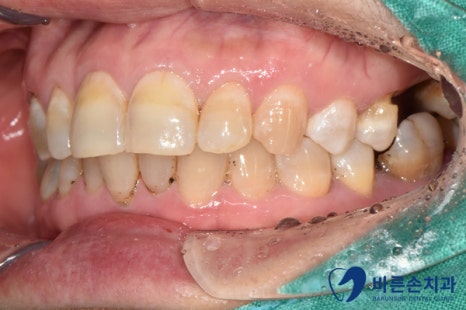

치석, 착색이 심한 초진사진.

초진 사진 입니다.

어금니가 대부분 부러져서 뿌리가 남아 있거나, 치주염으로 인해 흔들리는 상황 입니다.ㅠㅠ